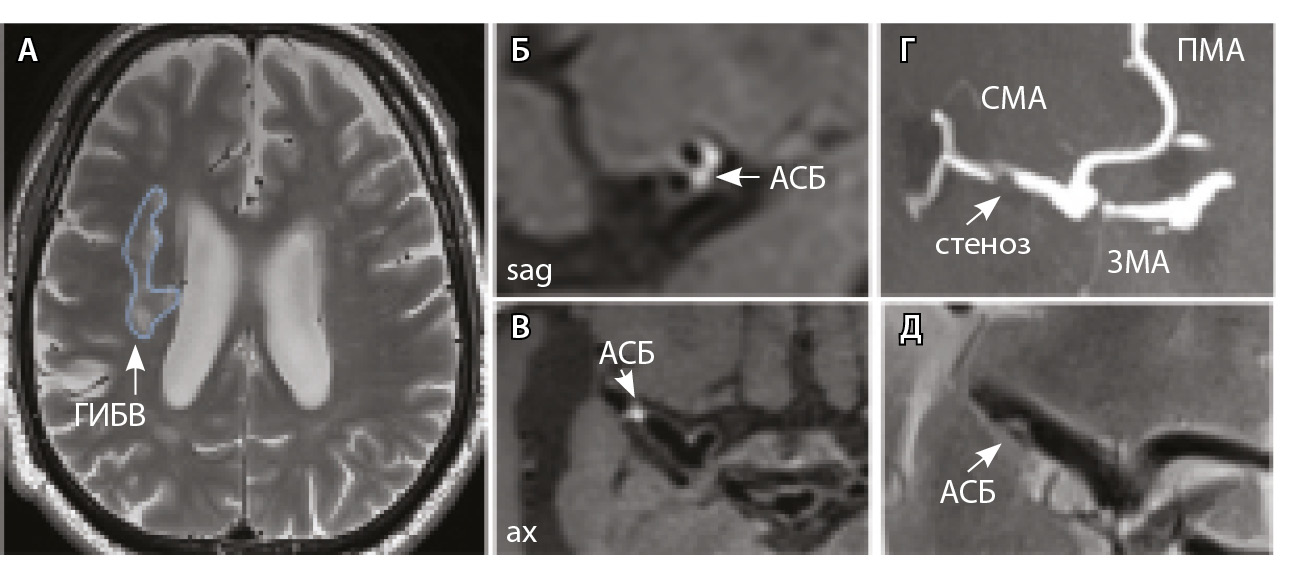

Рис. 3. Пациент Ц., 53 года, с признаками церебральной микроангиопатии (F3 по шкале Fazekas), атеросклерозом интракраниальных артерий, без формирования гемодинамически значимых стенозов. А – магнитно-резонансная томография (МРТ) головного мозга, режим Т2-взвешенного изображения: видны обширные сливные зоны гиперинтенсивности белого вещества (ГИБВ) с наличием на этом фоне лакунарных инфарктов; Б, В, Г – МРТ сосудистой стенки, режим T1-TSE-db-FS после контрастного усиления: в сегменте М1 левой средней мозговой артерии (СМА) визуализируется эксцентричная атеросклеротическая бляшка (АСБ), интенсивно накапливающая контрастный препарат; Д – трехмерная магнитно-резонансная времяпролетная (3D ToF) ангиография: выявляется неровность контуров левой СМА в сегменте М1; ax – аксиальная, sag – сагиттальная, cor – коронарная плоскости; ВСА – внутренняя сонная артерия; ПМА – передняя мозговая артерия

Рис. 4. Пациент К., 69 лет, с признаками церебральной микроангиопатии (F2 по шкале Fazekas) и атеросклерозом интракраниальных артерий, с формированием гемодинамически значимого стеноза в сегменте М1 правой средней мозговой артерии (СМА): А – магнитно-резонансная томография (МРТ), режим Т2-взвешенного изображения: видны множественные сливные очаги гиперинтенсивности белого вещества (ГИБВ); Б, В – МРТ сосудистой стенки, режим T1-TSE-db-FS после контрастного усиления: в сегменте М1 правой СМА визуализируется эксцентричная атеросклеротическая бляшка (АСБ), интенсивно накапливающая контрастный препарат; Г – трехмерная магнитно-резонансная времяпролетная (3D ToF) ангиография: виден стеноз правой СМА в сегменте М1; Д – режим HR Т2-TSE: видна АСБ в сегменте М1 правой СМА; ax – аксиальная, sag – сагиттальная плоскости; ЗМА – задняя мозговая артерия; ПМА – передняя мозговая артерия